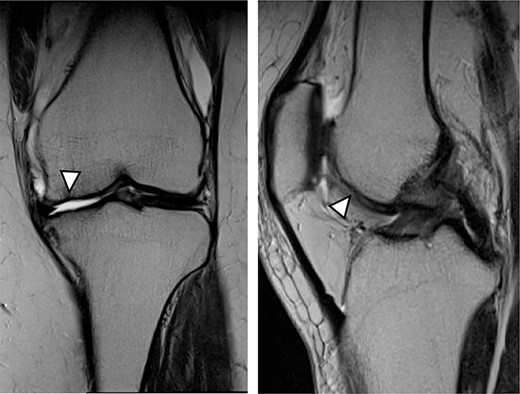

MRI findings at 1 year after the surgery indicated signal intensity area in the grafted area for the patient with JACC (Fig. 8), whereas the patient who underwent Reveille CP exhibited greater thickness at the grafted area as compared to the surrounding healthy cartilage (Fig. 9). The MOCART score at 1 year after the Reveille CP surgery (60 points) was higher than that of JACC (50 points).

One year after Reveille CP. The graft area was thicker than surrounding healthy cartilage (arrowhead).

Five years after JACC. MRI showed the graft area was thicker than the surrounding healthy cartilage (arrowhead).

A new product development of ACI with Reveille CP has three characteristics. The first characteristic is that Reveille CP creates autologous tissue with more surface area to absorb bioactive factors available within the marrow stimulation superclot. The second characteristic is that it creates autologous tissue grafts that retain high levels of variable, biologically competent chondrocytes. The third characteristic is that it creates autologous tissue grafts that support cellular proliferation, migration and new tissue matrix formation in culture. The adaptation in size of the cartilage defect is up to 4 cm2 for Reveille CP and 4 cm2 or higher for JACC. The advantage of Reveille CP includes one-stage surgical technique that requires no allergic test for atelocollagen gel nor periosteum sacrifice when compared with JACC. Meanwhile, Adachi et al. [17] reported that clinical data improved significantly postoperatively after implantation of tissue-engineered cartilage for full-thickness cartilage defects of the knee. In addition, good clinical outcomes were maintained for at least a median of 8.0 years, indicating the efficacy and durability of this procedure. Also, the MOCART score in case 2 improved to 75 points at 5 years after JACC surgery (Fig. 10). Knutsen et al. [18] revealed that further surgery was required in 23% of patients at 69 months after both ACI and microfracture treatments. In other words, a long-term follow-up of ACI using Reveille CP is required.